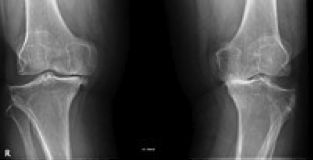

La Artrosis es una enfermedad degenerativa de las articulaciones. Consiste en la pérdida del cartílago articular, la formación de osteofitos y la deformación de la articulación afectada. Existen factores desencadenantes, como un traumatismo importante, y factores que aceleran la progresión de la artrosis, como la inestabilidad o la sobrecarga mecánica de la articulación afectada. También existe una predisposición genética a padecer la enfermedad. Las articulaciones más afectadas son la rodilla, la cadera, las articulaciones de las manos y la columna vertebral cervical y lumbar.

Aproximadamente un 10% de la población española sufre artrosis de rodilla (gonartrosis) sintomática, que se caracteriza por el dolor en relación con la actividad, al estar de pie y caminar, al subir a bajar escaleras. Además pueden existir derrame articular, crujidos y pérdida de fuerza en la pierna.

Cuando la artrosis es muy avanzada, la deformidad severa, el dolor importante y el paciente ya no puede realizar una vida normal, es el momento de plantear la intervención quirúrgica.